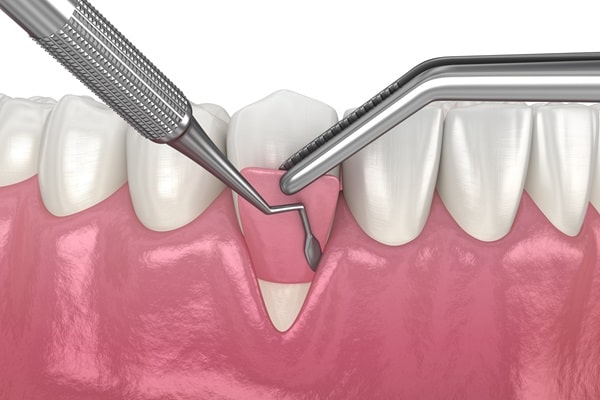

Gum Grafting

If you suffer receding or thinning gums that are affecting the stability of your teeth, you may benefit from gum grafting. Gum grafting involves covering the exposed teeth roots and adding volume to the gum. Most gum grafting procedures take a couple of weeks from start to finish and are generally very successful in restoring the gums.